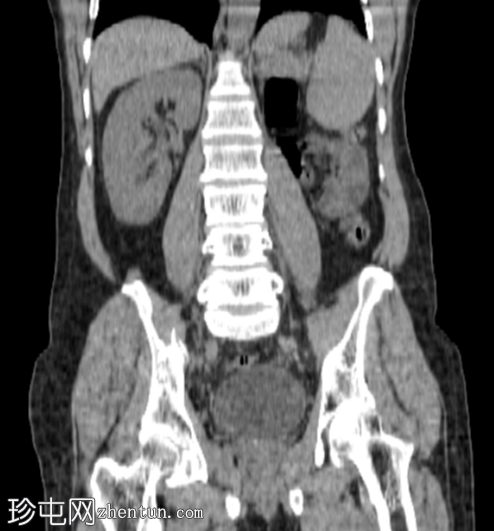

CT

冠状位

平扫

左肾发育不全。

左侧精囊发育不全。

肠系膜脂肪炎伴肠系膜脂肪间隙模糊及肠系膜淋巴结肿大。

肠系膜可见一小块钙化灶,提示钙化性淋巴结,系既往肉芽肿性感染的后遗症。